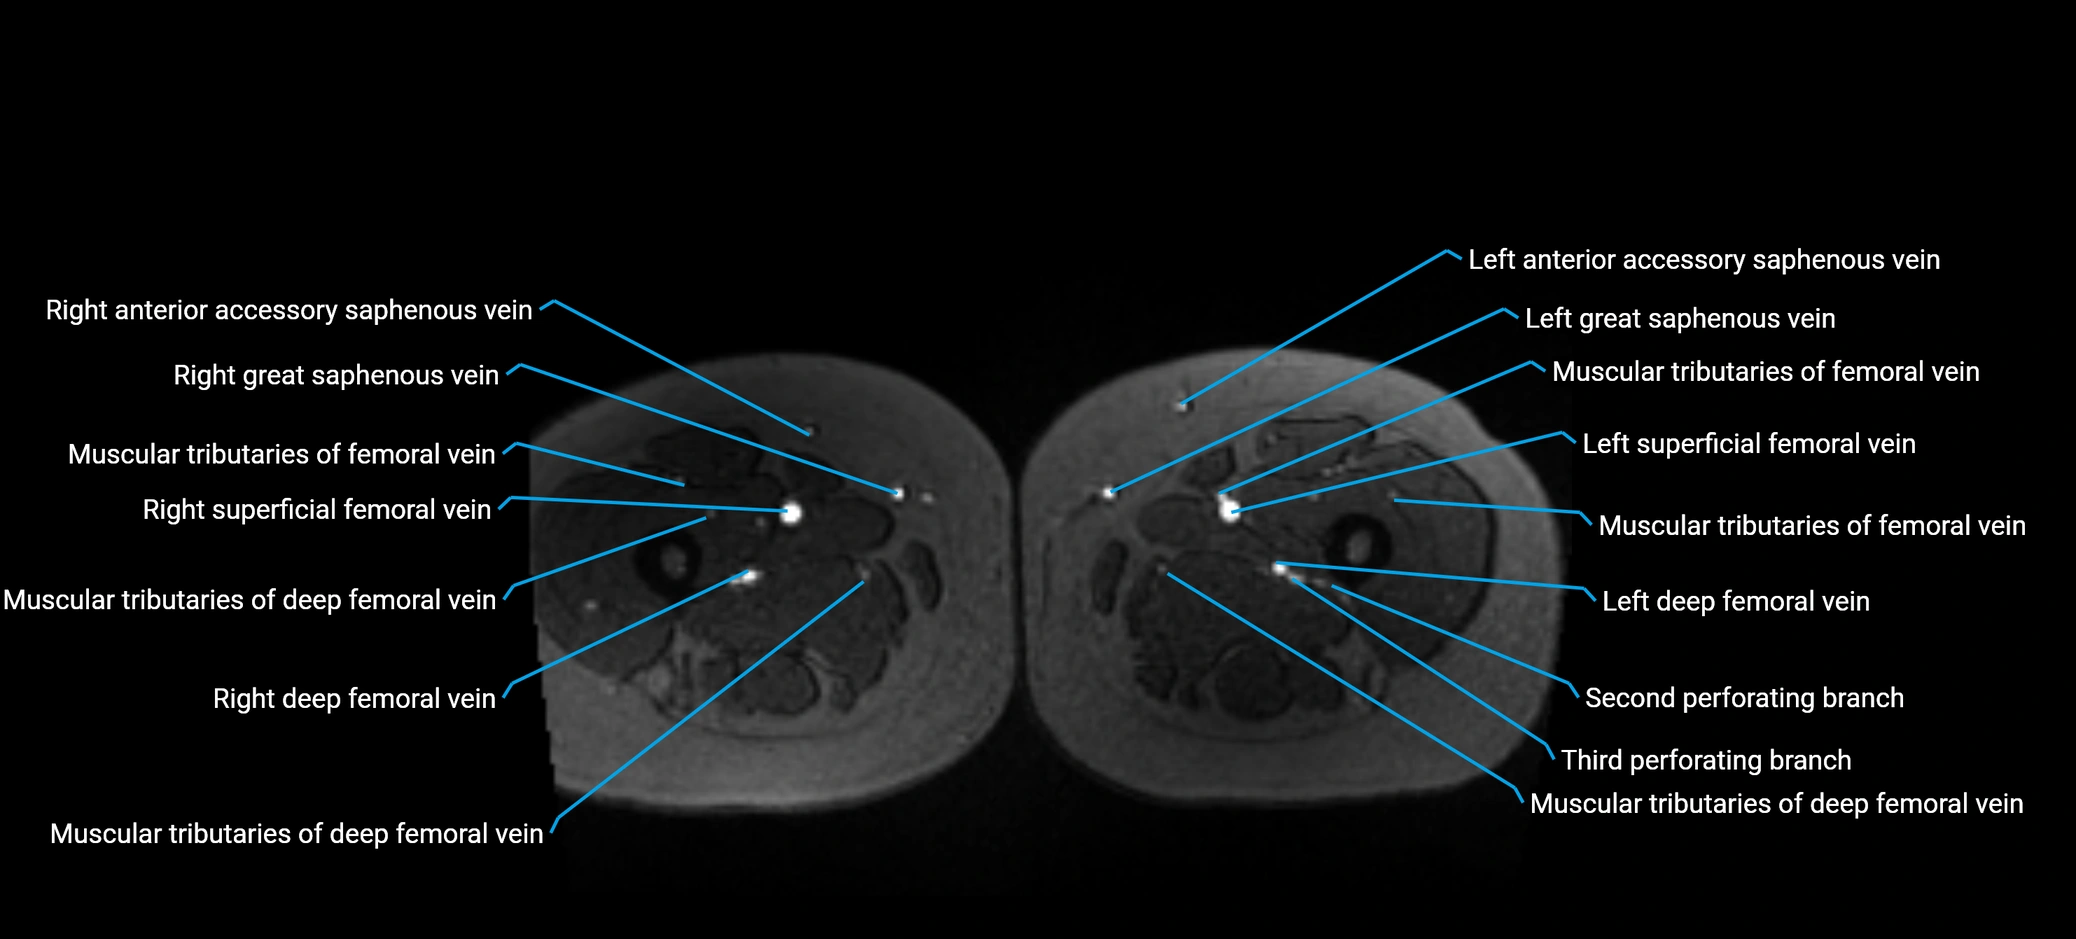

MRI image

image